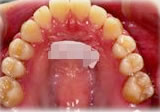

反対咬合(受け口)症例

初診時年齢24歳6ヶ月。前歯部反対咬合を主訴に来院。

骨格性反対咬合と診断し、外科的処置を併用して治療。

上顎 上顎 上顎